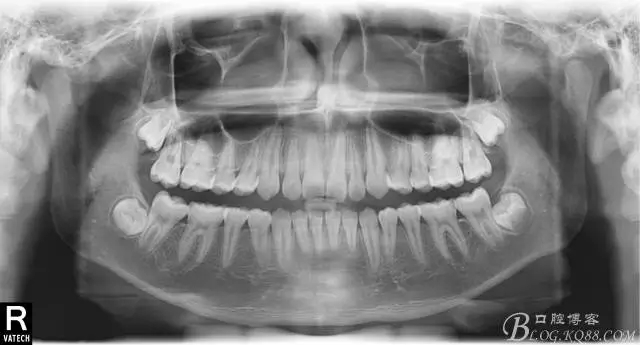

專科檢查:恒牙列,牙列式上下7-7.覆蓋二度,覆合三度,雙側(cè)磨牙關(guān)系二類,尖牙關(guān)系二類,下合3-3各牙間散在約1-1.5mm間隙,輕度唇傾,正面觀顯下頜頦部發(fā)育不足,側(cè)貌可觀察到下頜略顯后縮,上頜鼻唇角以及唇部大體正常。開口型向下,舌體正常,TMJ檢查及其它未發(fā)現(xiàn)異常。

輔助診斷:由于當(dāng)時條件有限,沒能拍攝全景,側(cè)位片,更不用說頭影測量數(shù)據(jù)來診斷了,只能憑借經(jīng)驗和些小技巧來判斷了,這類案例到底是患者所說的前突還是下合后縮。

看看口內(nèi)照吧!真象“大暴牙”v假象“大暴牙”

三度深覆合,三度深覆蓋,尖牙,磨牙均二類關(guān)系!

診斷:1.上頜大體正常,下頜后縮.

2,安氏二類錯合。